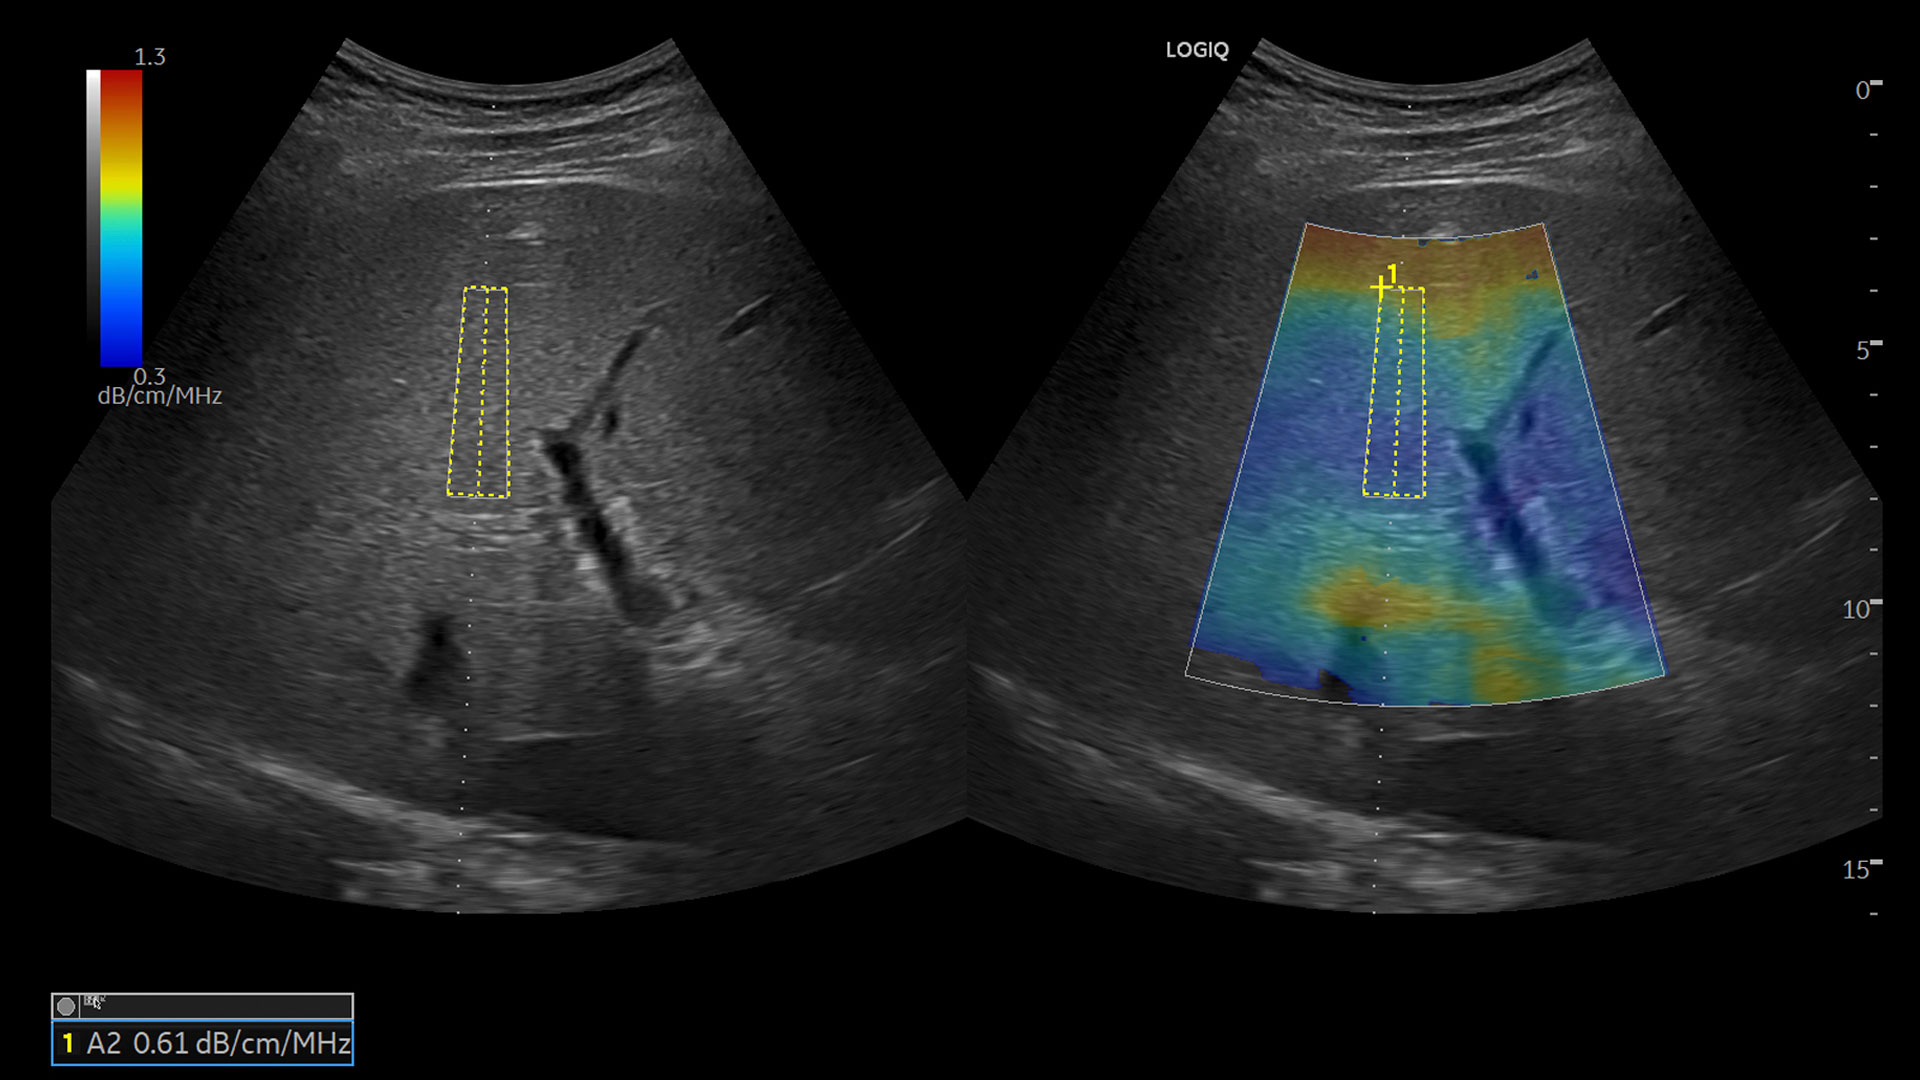

• Ultrasound-Guided Attenuation Parameter (UGAP)

pdp-feature-hero-LP-HD-Liver-Powerful-Support-1650x1100